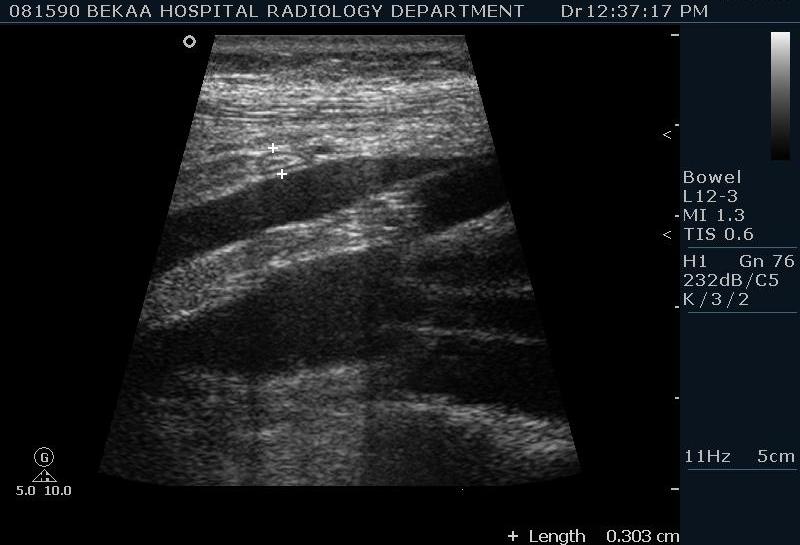

Диагностика острого аппендицита по УЗИ: очень актуальная тема; УЗ аппараты практически есть во всех клиниках; метод доступный и не сложный; главное владеть правильной техникой. Не буду загружать лишней теорией и разными ссылками; поделюсь практическим опытом. У меня линейный датчик 3-12 мегагерц с плавающей частотой; аппарат Филипс HD 11, всегда включаю соно-КТ (9800 цифровых каналов) и гармонику когда смотрю кишечник. Нормальный аппендикс видеть можно; но вопрос зачем??? Как правило, если при наличии достаточного опыта аппендикс не виден; значит скорей всего аппендицита нет. Когда "идешь" на аппендицит то главное по началу набраться терпения и......хорошая компрессия! По началу надо минут 10-15; потом когда появится достаточный опыт; за 2-5 минут можно справится и получить отличную визуализацию. Мочевой пузырь лучше опорожнить; часто он приподнимают тонкий кишечник и может закрыть "окно" через которое будет видно апендикс. Сначала находим слепую кишку потом находим илео-цекальное соединение;

после начинаем производить хорошую компрессию датчиком попрося пациента сообщить в какой точке боль наиболее выражена; медленными движениями датчика сканируем область наибольших болевых ощущений и как правило находим утолщенный отросток. Лучше начинать с поперечной визуализации и идти к верхушке аппендикса что бы убедится что это аппендикс и он заканчивается, а не тонкая кишка (которая если и закончится то только переходя в слепую); потом надо аккуратно развернуть продольно датчик и посмотреть от верхушки аппендикса к слепой. Норма диаметра: 3-4 мм; 5-6 мм под вопросом (клиника решает; но я в катаральный аппендицит не верю); 7-8 мм и больше, не компремируемый (фиксированный отросток)-острый аппендицит! Помимо наличие утолщенного аппендикса; признака "бычьего глаза" (bull-eye sign) при поперечном сканировании; надо обращать внимание на присуствие аппендоколитов в просвете; деструкцию стенки и свободной жидкости в зоне интереса.